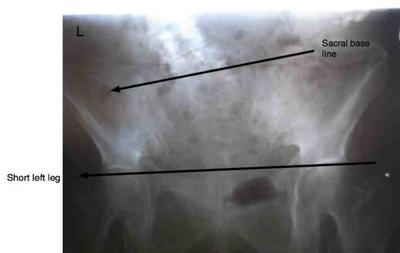

It almost certainly starts in the lower back, and a short leg needs to be considered. A small insert in her shoe may help.